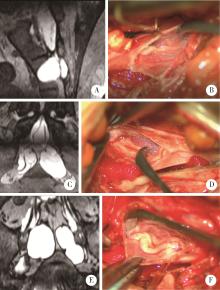

图1

内含神经根囊肿的不同类型"